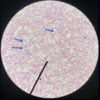

Genus: plasmodium

Malaria

Lives inside red blood cell

Genus plasmodium